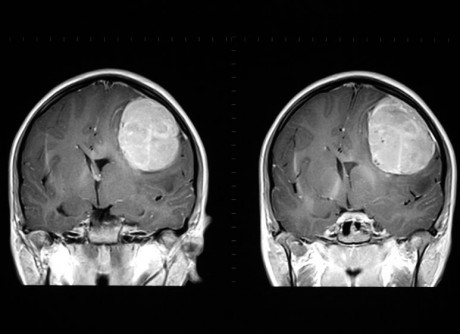

Новообразования в мозге

Нередко причины частых головных болей — доброкачественные или злокачественные новообразования в мозге. Такой симптом опухоли, как боль — самый распространенный. Тем не менее, многие не придают болям особого значения, а когда проходят обследование — уже слишком поздно. Поэтому важно прислушиваться к собственному организму и знать основные отличия такой боли:

- возникает с самого утра, когда человек еще не встал с кровати;

- наряду с этим больного постоянно тошнит, и он испытывает приступы рвоты;

- нарушается координация движений, речь, слух и зрение;

- интенсивность боли постоянно растет, больному необходимы сильные обезболивающее средства.